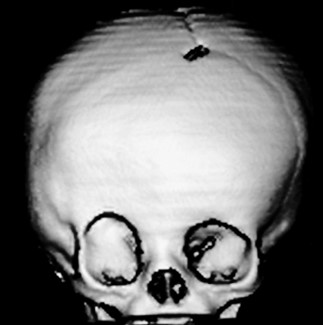

> Escafocefalia, é a sinostoses mais comum, vista mais no sexo masculino,o que acontece é o fechamento da sutura sagital levando o crânio ao formato de barco. A cirurgia é indicada de preferencia antes do sexto mês de vida, mas se a criança tiver mais idade, não impede de ser operado.